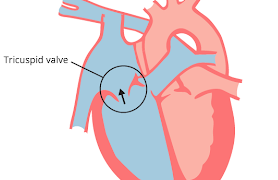

犬の心臓弁膜の疾患(acquired heart diseases)家畜の後天性心疾患については、各種動物でかなりの発生をみていますが、ここではその主なものについて記載します。犬の心臓弁膜の疾患(valvular heart disease...